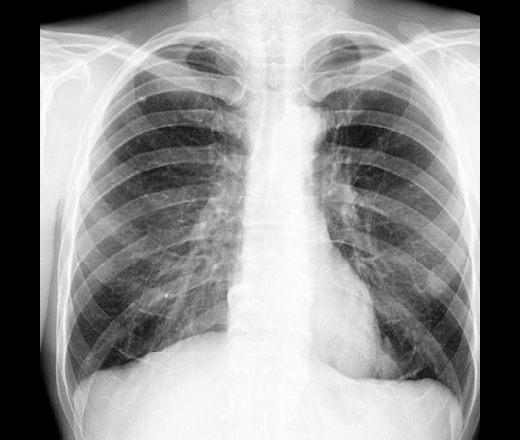

Сомнения насчет мозоли: почему на задней проекции по нижней поверхности ребра костная мозоль на контур не выходит? Разве так бывает, я бы усомнился. И плонтность ее не очень равномерная. Хотя бы скопией проверить смещение вместе с ребром при дыхании и наблюдать если что.

Снимок от 2014: